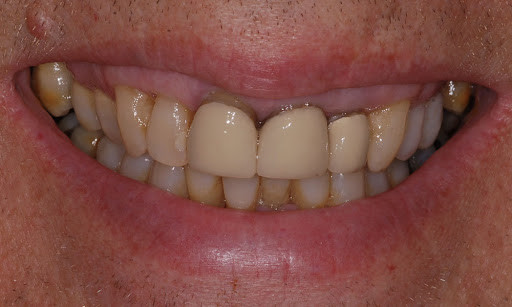

What Causes The Dark Line On My Gums?

You have seen smiles that you know have dental crowns in the front. You look at them and say to yourself that something is not natural. Many times, it is the dark rim of gum tissue that gives it away. The dark rim of gum tissue does not occur around natural teeth, only around teeth that have been covered with dental crowns.

The dark line is associated with an old porcelain dental crown. This style of dental crown is referred to as a porcelain fused-to-metal dental crown because it uses tooth-colored porcelain on the outside and it uses metal under the porcelain for strength. The dark line originates from the edge of the dental crowns where the porcelain and the metal meet at a knife-edge at the gum line. At the knife-edge, a very thin amount of the metal always shows. One of the illusionary techniques cosmetic dentists have used was to hide the thin dark line under the gum line. Over time, the gum tissue would recede and expose the dark line. In some patients the dark line would show through the gum and make it appear dark as well.

How Do You Get Rid of It?

The only way to eliminate the esthetic problem is to replace the dental crowns. When replacing just one single dental crown in the front, you should expect that it might take more than one try-in of the new dental crown before it is permanently cemented into place. Because your central incisors are the most prominent teeth in the mouth, matching them is the most difficult esthetic challenge. Only the best dental technicians are able to mimic one central incisor tooth next to another.

What Are Some of the Replacement Dental Crowns Like?

Some of the clever ways dentists and dental technicians have been able to mimic natural teeth is through the new advancements in dental materials. New all-tooth-colored ceramic dental crowns are the latest technological advancement cosmetic dentists have to recreate natural teeth. In comparison to porcelain fused-to-metal dental crowns, all-ceramic dental crowns do not contain any metal, thus no dark line can appear.